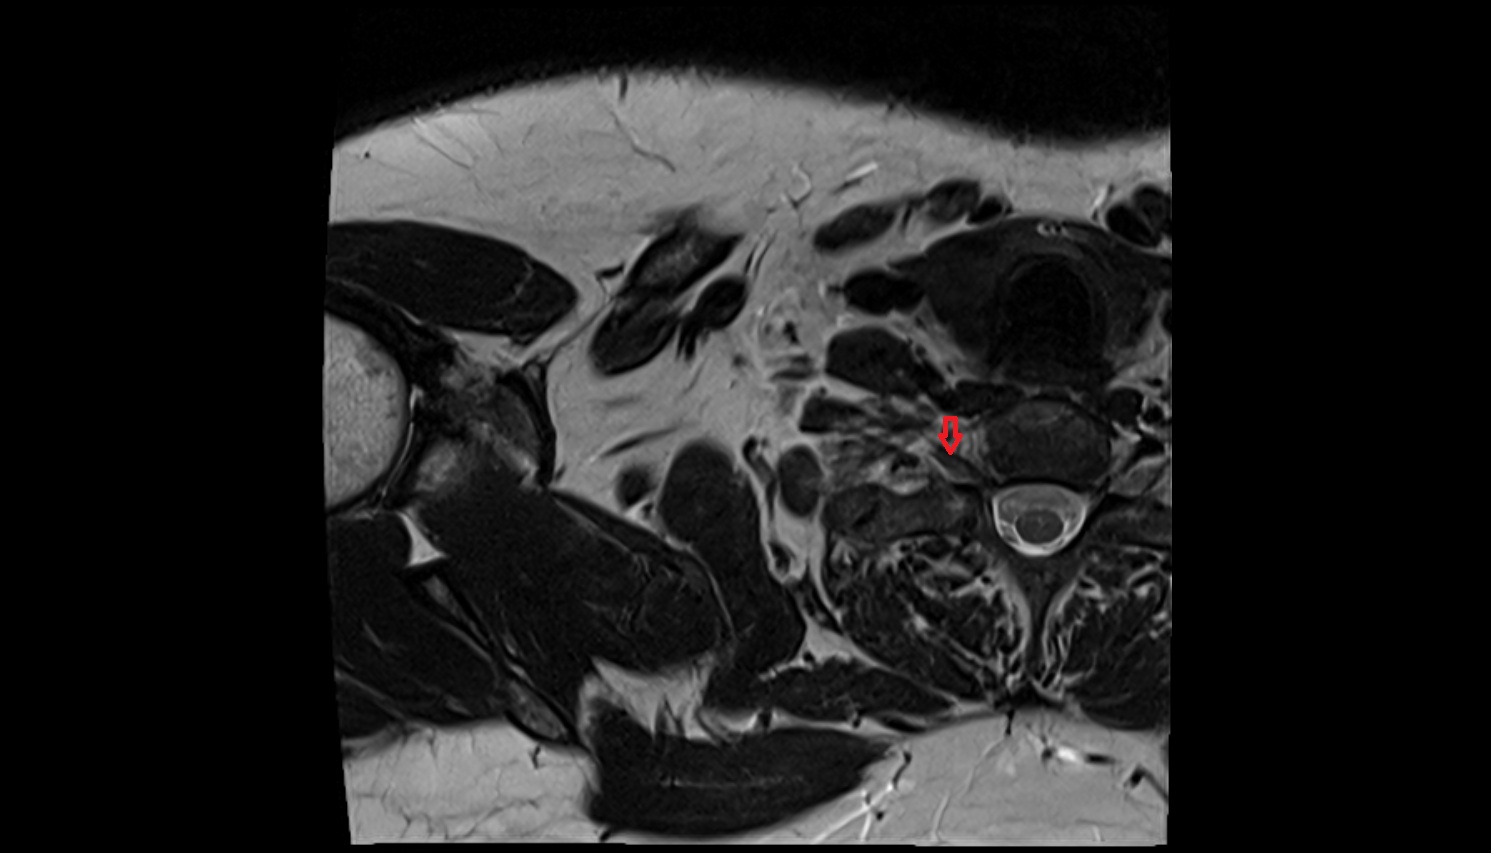

- Hip joint